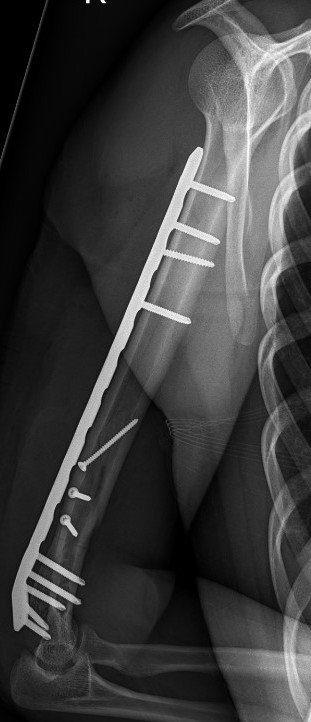

Humeral Fracture SegmentalHumeral Plate LateralHumeral Plate Long AP

Segmental fracture ORIF